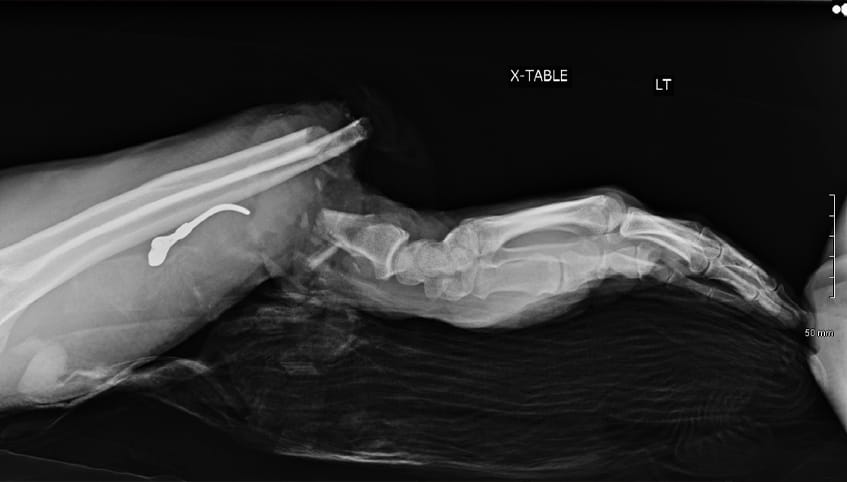

A surgical team performed an intricate 8-hour microsurgery to reattach Steve's forearm. Having completed fellowships in hand and upper extremity surgery, and addressing traumatic injuries such as this on a weekly basis, the team offered some of the region's best care in replantation and functional recovery.

Surgeons performed Steve's surgery under a microscope. They first plated and screwed the severed bones into place and then used sutures finer than a human hair to reconnect transected nerves, veins, blood vessels and tendons.

The care team is able to begin care even before the patient arrives, which is essential since the separated body part is viable for only about 4 hours. They collaborate with the referring providers to start antibiotics, transfer X-rays or instruct the use of splints. By getting started immediately, the team can make the most of limited time.